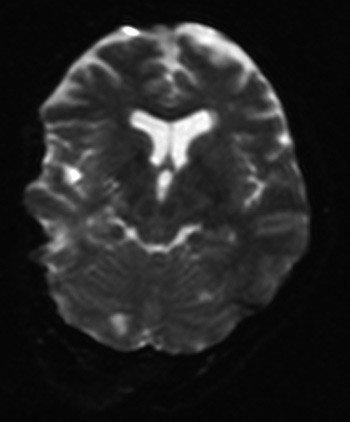

Kontroll- MR caput en uke senere viste at de bilaterale foci med diffusjonsrestriksjon i det vesentlige var gått tilbake. Det gjensto kun sparsomme aktuelle signalforandringer frontoparietalt på høyre side samt i høyre lillehjernehemisfære (fig 2). FLAIR-sekvensene viste imidlertid flere bilaterale subkortikale høysignalforandringer av iskemisk karakter og av ukjent dato.

Andre har tidligere vist at man ved kontroll-MR av cerebrum kan ha tilbakegang av signalforandringer ved cerebral fettembolisme (4).